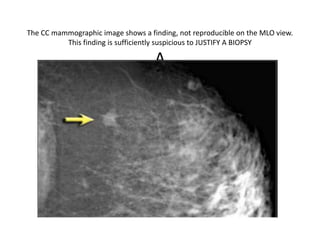

The CC mammographic image shows a finding, not reproducible on the MLO view.

This finding is sufficiently suspicious to JUSTIFY A BIOPSY

A

The pathologist could report to you that it is sclerosing adenosis or ductal

carcinoma in situ.

Both diagnoses are concordant with the mammographic findings.